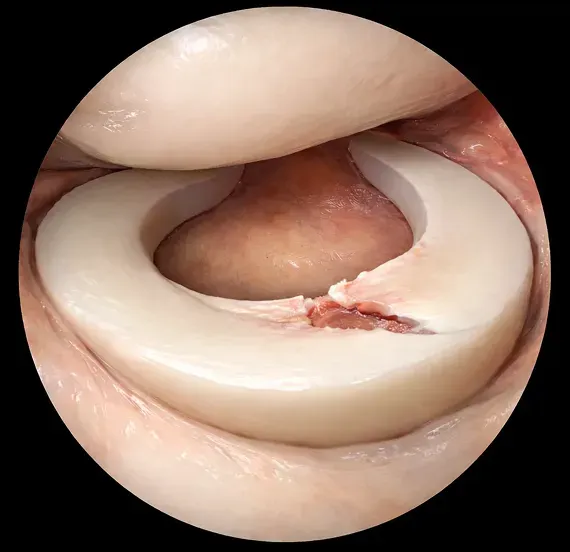

関節鏡所見

正常

関節鏡所見での正常時

半月板損傷

関節鏡所見での半月板損傷時